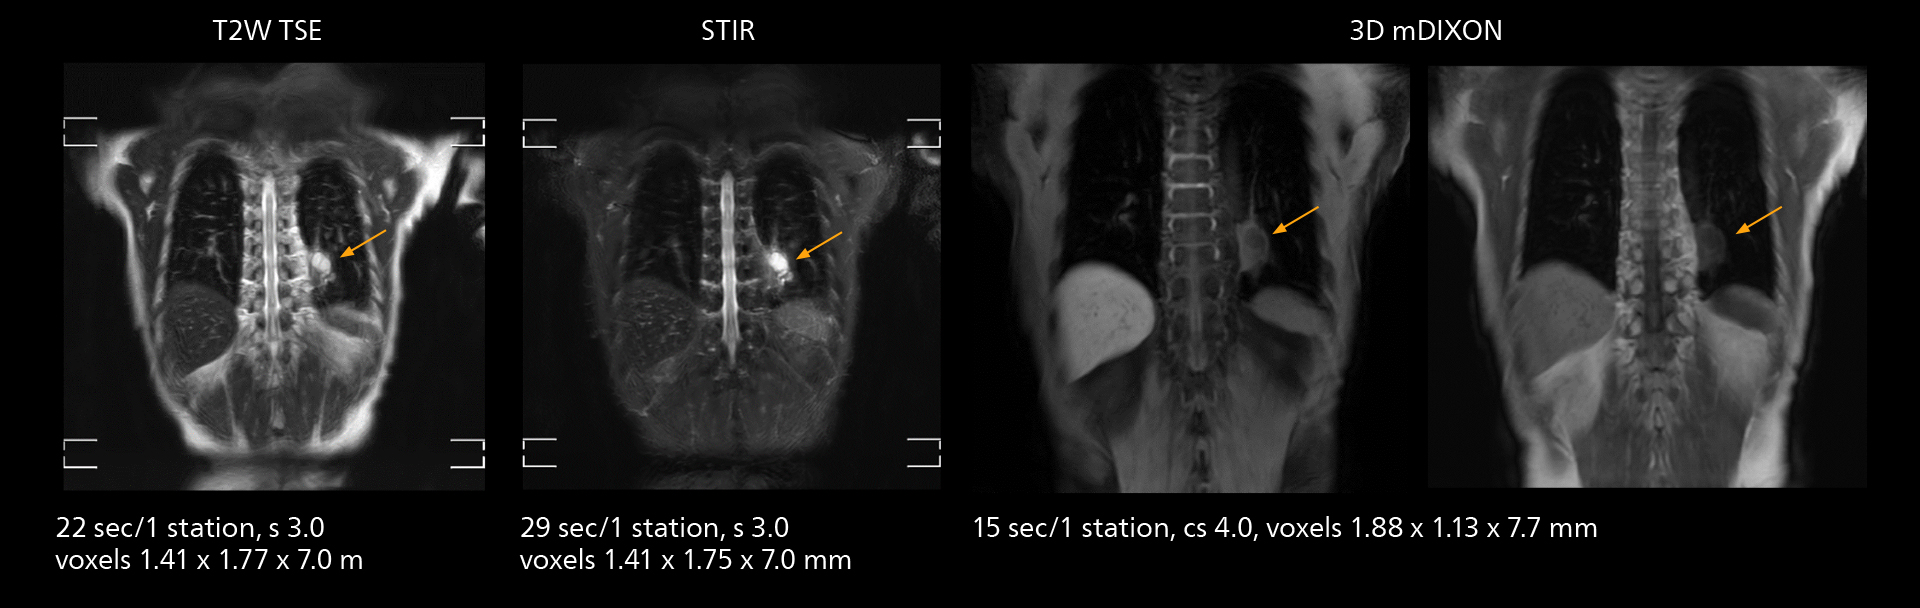

SmartPath to Elition X comes with Smart Workflow technologies that support technologists and can save them time. VitalEye for touchless patient sensing is one example. “The implementation of VitalEye respiratory synchronization has had a significant impact,” says MR technologist Yoshihiro Otsu, Chief of the Radiological Department. “It not only improves workflow, but it also has increased the quality of examinations. Particularly for the large number of MRCP examinations performed in this hospital, VitalEye has increased the possibility to obtain sharp images with less blurring. Clinicians here really appreciate this improvement in MRCP image quality.” The VitalScreen on the scanner has helped reduce the risk of patient misidentification. “It allows patient information to be viewed in the magnet room when standing next to the patient,” he says. “And the automated patient centering in the magnet is very useful as well.” Apart from reducing stress for technologists, Smart Workflow helps improve respiratory synchronization and reduce examination stress for the patient.

With SmartPath to Elition X, the MRCP examinations at Sannodai Hospital benefit from VitalEye: respiratory synchronization is possible without respiratory belt positioning and image quality is excellent.